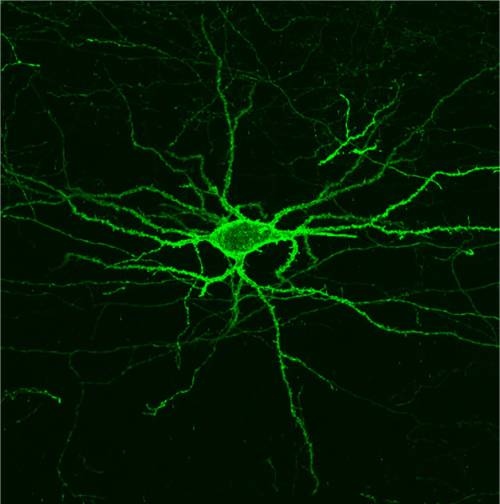

La actividad eléctrica de las neuronas podrá ser ahora medida a través de señales fluorescentes. (Foto: cortesía de los investigadores)

Gracias a ello, han dado con una proteína sensible a la luz que puede ser incrustada en las membranas de las neuronas, donde emite una señal fluorescente que indica cuánto voltaje está experimentando una célula cerebral en particular. Esto podría permitir a los científicos estudiar cómo se comportan las neuronas, milisegundo a milisegundo, a medida que el cerebro lleva a cabo una función concreta.